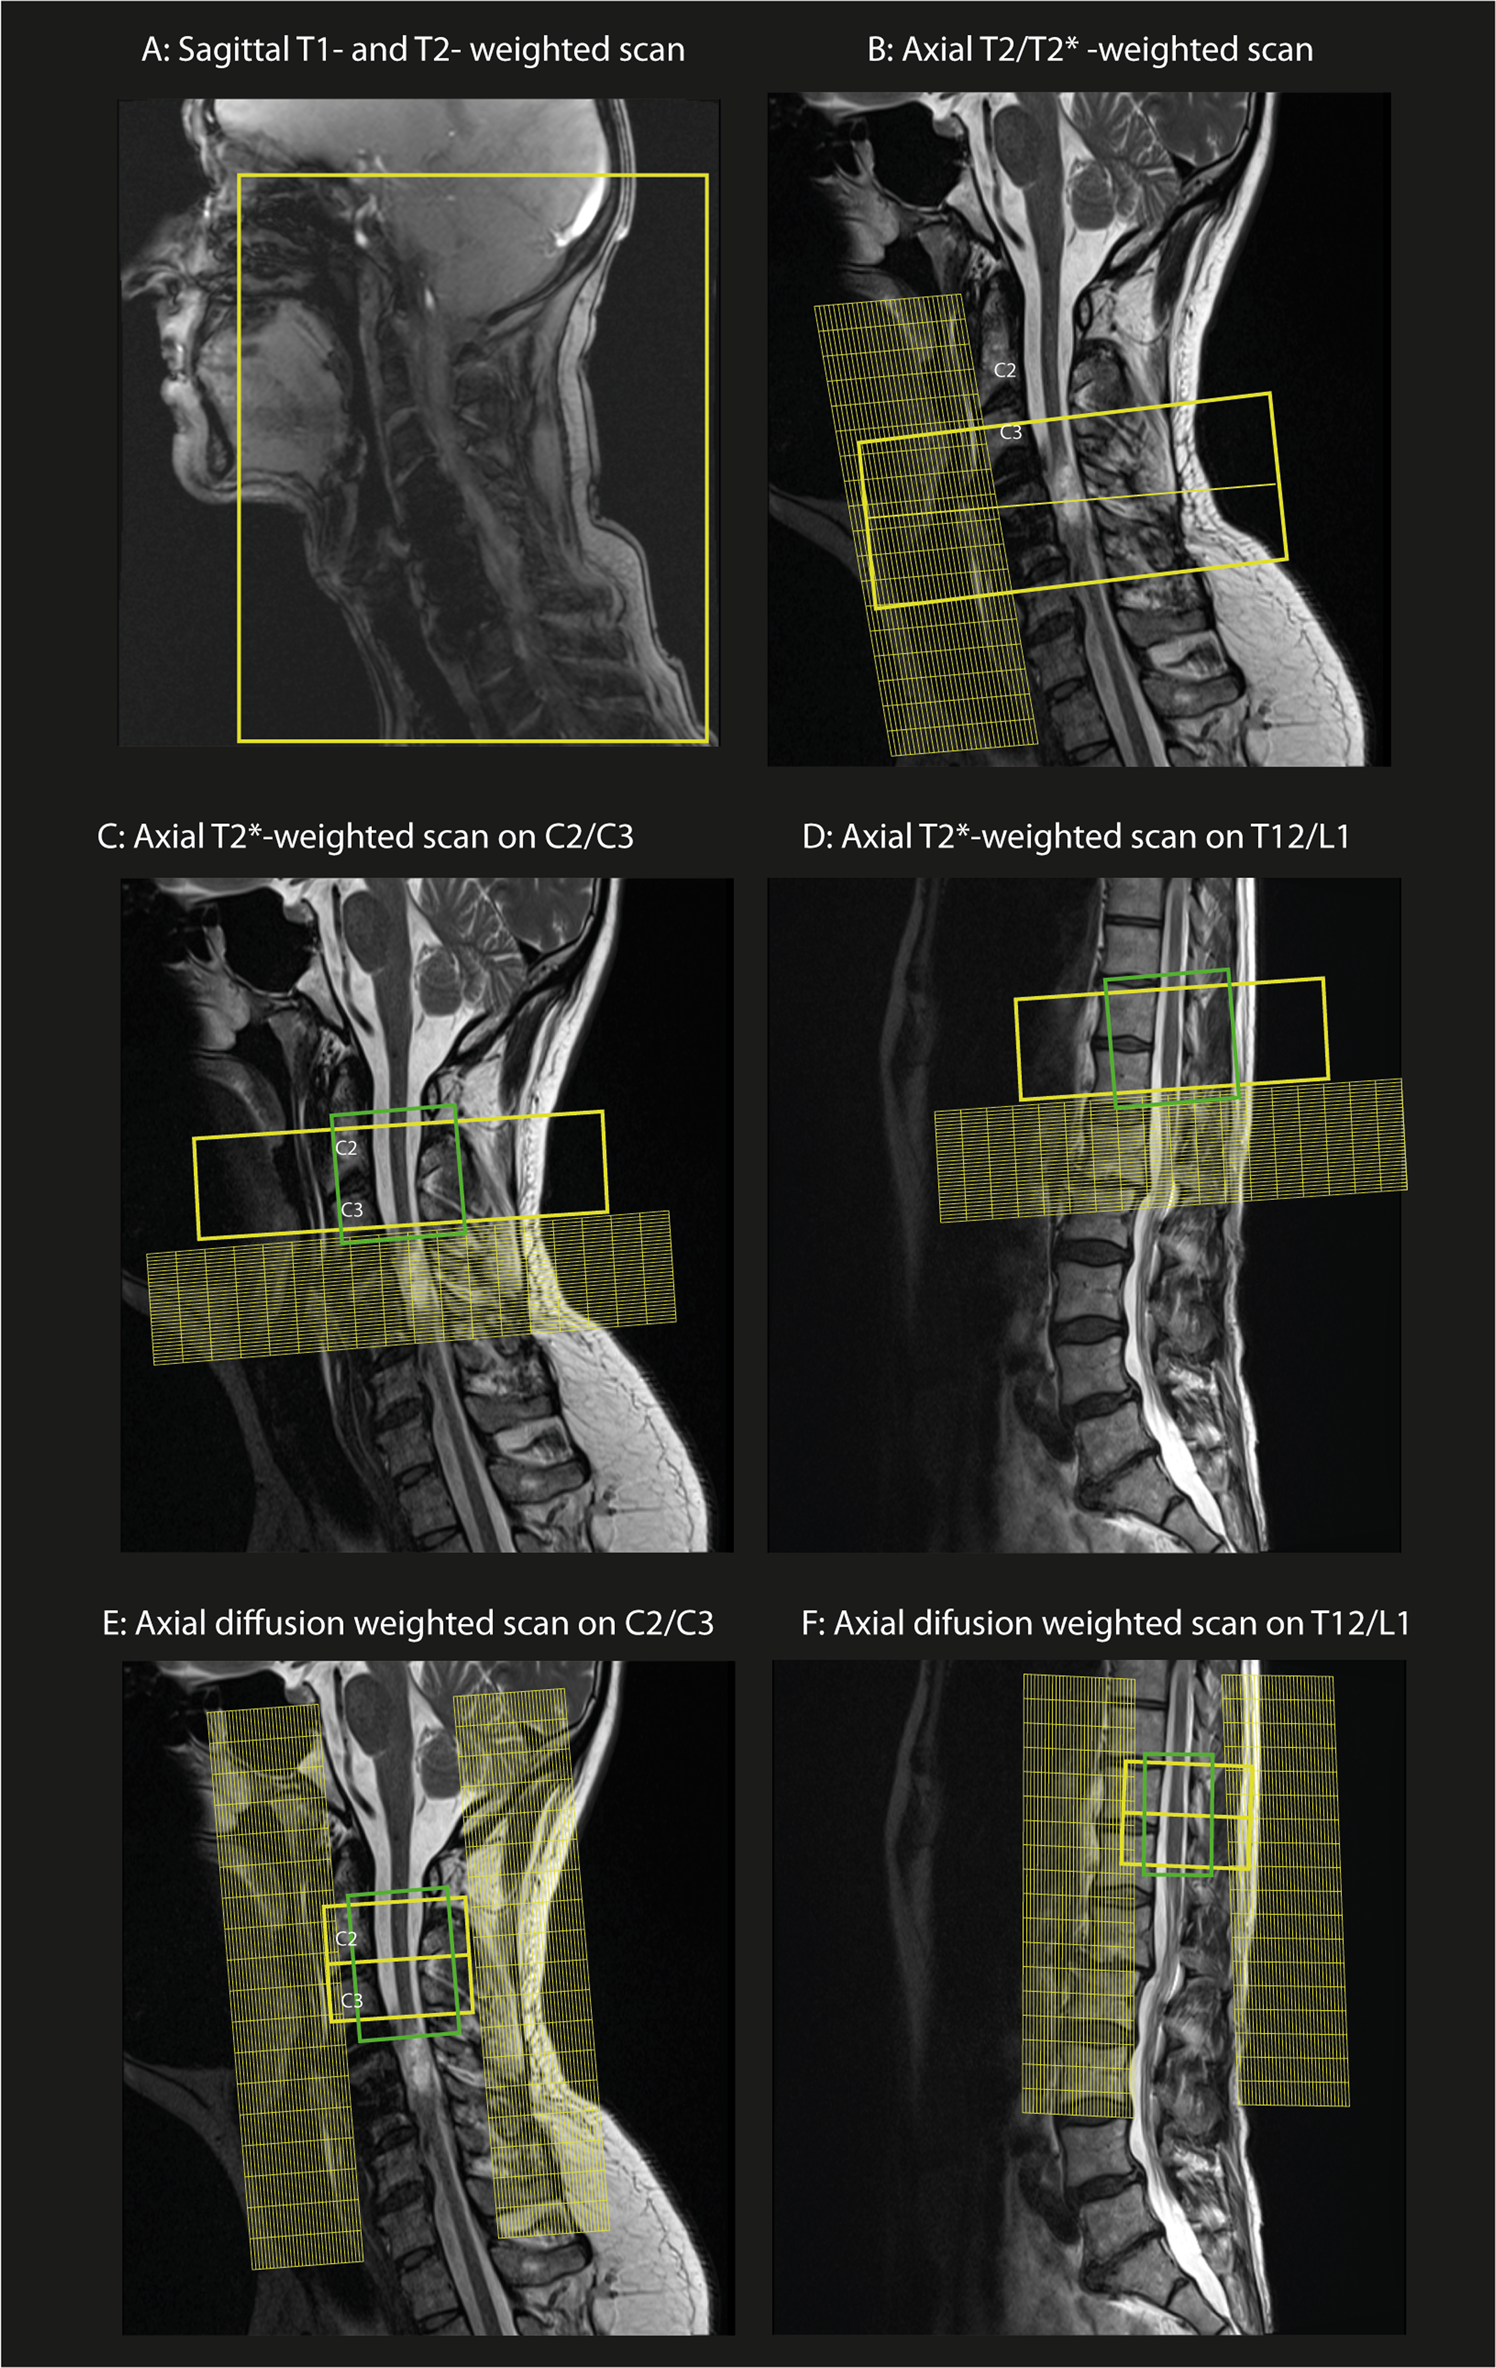

Fig. 2

Spinal cord MRI protocol set-up: a, b Sagittal and axial T1-, T2- and T2*- weighted scans on the cervical spinal cord lesion. c, d Axial T2*-weighted scan set-up at the cervical and lumbar level above and below the lesion, respectively. e, f Diffusion MRI protocol set-up on the cervical spinal cord (C2/C3 level) and lumbar enlargement (T12/L1 level) with corresponding saturation bands